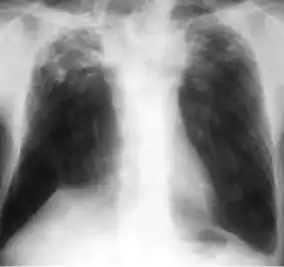

In active pulmonary TB, infiltrates or consolidations and/or cavities are often seen in the upper lungs with or without mediastinal or hilar lymphadenopathy.[1] However, lesions may appear anywhere in the lungs. In HIV and other immunosuppressed persons, any abnormality may indicate TB or the chest X-ray may even appear entirely normal.[1]

2. Any cavitary lesion - Lucency (darkened area) within the lung parenchyma, with or without irregular margins that might be surrounded by an area of airspace consolidation or infiltrates, or by nodular or fibrotic (reticular) densities, or both. The walls surrounding the lucent area can be thick or thin. Calcification can exist around a cavity.

Chest X-ray of a person with advanced tuberculosis: Infection in both lungs is marked by white arrow-heads, and the formation of a cavity is marked by black arrows.